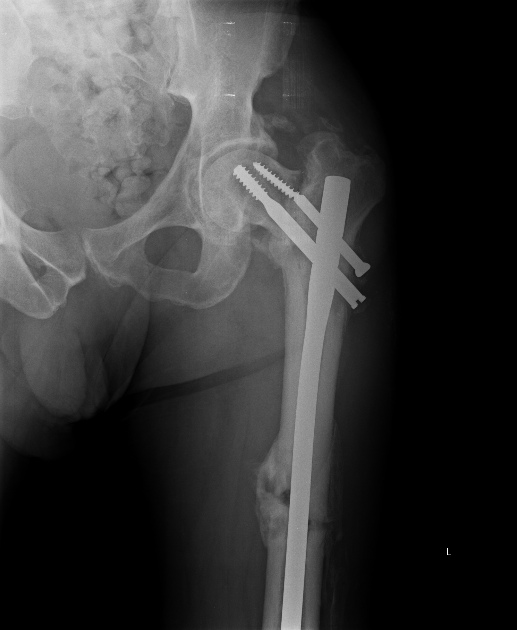

Пациент 63 года мужчина, остеосинтез чрезвертельного перелома проксимальным бедренным стержнем в октябре 2012. Постепенно появились и усилилиь боли в т.б.с., рентгенограммы показывают прорезание шеечного винта.

Винт был введен недостаточно глубоко, и главное - длина бедра не была полностью восстановлена.

Реостеосинтез проксимальным гвоздем тут проблематичен, надо исхитриться сделать то, что не сделали при первичном остеосинтезе, т.е. вальгусную репозицию, восстановить длину бедра, и винт ввести не в имеющийся канал, а кпереди, и буквально субхондрально.

135 градусов, боюсь, не оптимальный угол для железки. Можно, наверно, ввести передне-задние винты в шейку на уровне имеющегося канала винта, и ввести новый винт под них.

Клинковая пластина 130 градусная как вариант остается. Или эндопротез уж сразу?

Насчет ревизионного штифтования - вот пример, вчера сделали.

Молодым желательно сохранить головку, и вопрос артропластики надо снять из повестки. Выбор фиксатора зависит от наличия сращения в зоне перелома, а на этих снимках трудно различить, имеется ли сращение. В сравнении с предыдущими снимками показатель шеечно-диафизарного угла изменился, около 85 градусов - это укорочение. Имплант на стороне, а головка находится в ротации.